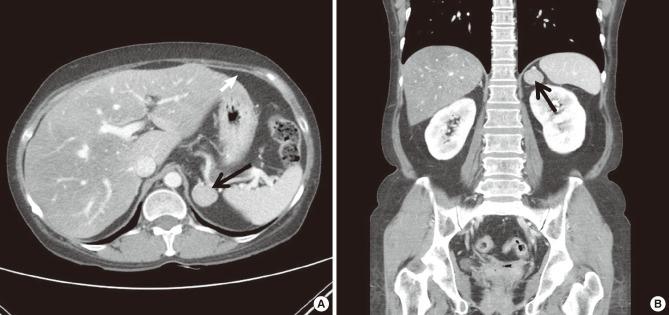

糖皮质激素(GC)过多,包括库欣综合征,是继发性骨质疏松症的常见原因。30%至50%的库欣综合征患者会发生非创伤性骨折,这往往是库欣综合征的首发表现。然而,仅有少数病例仅根据骨骼表现确诊为库欣综合征。我们描述了一例库欣综合征病例,该病例为一名44岁女性,最初因多处非创伤性肋骨骨折前来我院就诊。她没有表现出库欣综合征的任何其他表现,如满月脸、水牛背或腹部条纹。最初,我们对她进行了不明来源癌症骨转移的评估,但没有转移性癌症的证据。相反,我们发现了左侧肾上腺意外瘤。通过激素检查,她被诊断为库欣综合征。有趣的是,她在骨扫描和骨密度测量中明显的库欣综合征骨骼表现,在左侧肾上腺切除术后完全恢复。因此,对于有或没有库欣综合征任何其他典型特征的非创伤性多发骨折的年轻患者,应考虑库欣综合征作为继发性骨质疏松症病因的可能性。